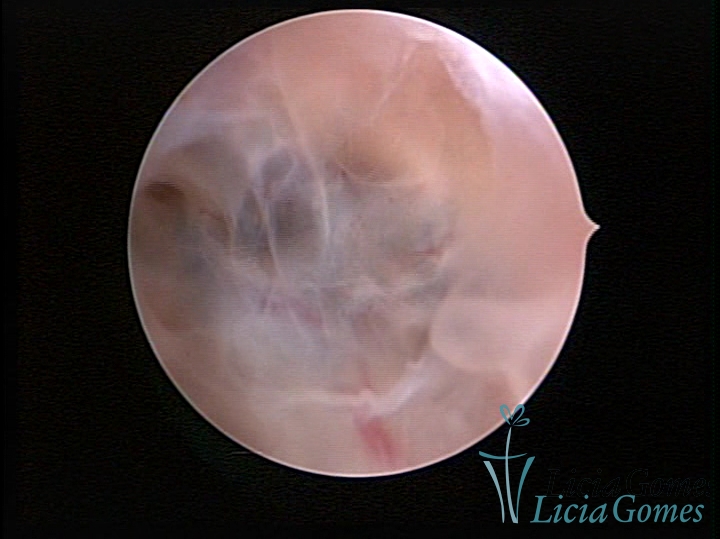

Sinéquia TIPO FIBROSA

• SINÉQUIA TIPO FIBROSA